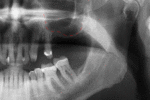

Success or failure of implants depends on the health of the person receiving it, drugs which affect the chances of osseointegration and the health of the tissues in the mouth. The amount of stress that will be put on the implant and fixture during normal function is also evaluated. Planning the position and number of implants is key to the long-term health of the prosthetic since biomechanical forces created during chewing can be significant. The position of implants is determined by the position and angle of adjacent teeth, lab simulations or by using computed tomography with CAD/CAM simulations and surgical guides called stents. The prerequisites to long-term success of osseointegrated dental implants are healthy bone and gingiva. Since both can atrophy after tooth extraction, pre-prosthetic procedures such as sinus lifts or gingival grafts are sometimes required to recreate ideal bone and gingiva.

The long-term success of implants is determined, in part, by the forces they have to support. As implants have no periodontal ligament, there is no sensation of pressure when biting so the forces created are higher. To offset this, the location of implants must distribute forces evenly across the prosthetics they support.[14](pp15–39) Concentrated forces can result in fracture of the bridgework, implant components, or loss of bone adjacent the implant.[15] The ultimate location of implants is based on both biologic (bone type, vital structures, health) and mechanical factors. Implants placed in thicker, stronger bone like that found in the front part of the bottom jaw have lower failure rates than implants placed in lower density bone, such as the back part of the upper jaw. People who grind their teeth also increase the force on implants and increase the likelihood of failures.[6](p201–208)

When a more exacting plan is needed beyond clinical judgment, the dentist will make an acrylic guide (called a stent) prior to surgery which guides optimal positioning of the implant. Increasingly, dentists opt to get a CT scan of the jaws and any existing dentures, then plan the surgery on CAD/CAM software. The stent can then be made using stereolithography following computerized planning of a case from the CT scan. The use of CT scanning in complex cases also helps the surgeon identify and avoid vital structures such as the inferior alveolar nerve and the sinus.[17][18](p1199)